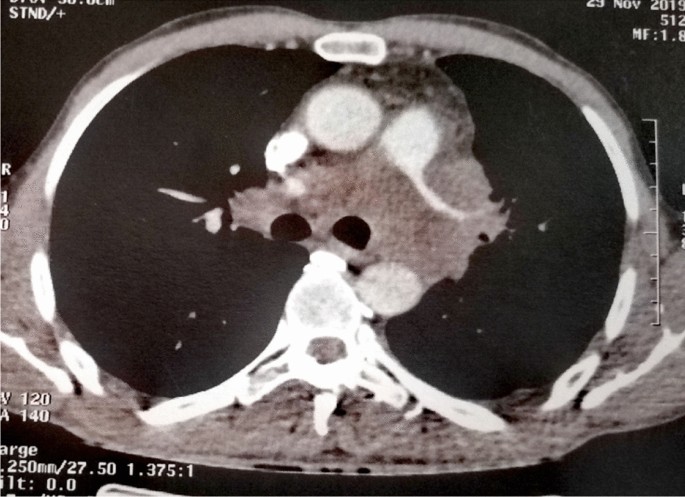

We received a 26-cm-long segment of the small intestine measuring, two lymph nodes and a peritoneal nodule. The intestine includes an ulcerating and infiltrating tumor of 6 cm. Several samples were taken. Histological examination showed a malignant tumor with poorly cohesive sheets of large cells with an epithelioid and rhabdoid appearance (Fig. 1a). The tumor cells were anysocaryotic without major pleomorphism. Their cytoplasm was globoid and eosinophilic and the irregularly shaped nuclei had vesicular chromatin with large nucleoli (Fig. 1b). Mitoses and areas of geographic necrosis were numerous. Lymph nodes and the peritoneal nodule were massively infiltrated by this tumour. The immunohistochemical study showed a diffuse tumour cell positivity with vimentin, CD34, and SOX2 with more heterogeneous positivity for SALL4 (Fig. 1c, d). It revealed negative expression to epithelial markers CK AE1/AE3, Pan-CK and EMA ruling out the diagnosis of an undifferenciated carcinoma (Fig. 1e). Large cell lymphoma was also excluded by negative expression of lymphoid markers (CD45, CD20, PAX5, CD79a, MUM1, CD138, CD163, CD43, CD3, CD5, CD7, CD68, CD163, TdT, MPO, CD30, CD15, ALK, XCL13, CD21, CD23) (Fig. 1f). Epithelioid sarcoma showing strong and diffuse positivity to EMA and Vimentin was also excluded. In the same way, malignant peripheral nerve sheath tumour and melanoma were ruled out by negative expression of S-100. Also tumour cells did not express neither CD117 nor DOG-1 making the diagnosis of gastro-intestinal stromal tumor unlikely. Negativity to CDK4 and MDM2 eliminated the diagnosis of liposarcoma. Negativity to CD31and Desmin excluded, respectively, a vascular and a muscular differenciation of this tumor. In the same way negativity to synaptophysin, chromogranin and CD56 ruled out a neuroendocrine differenciatin. The proliferation index was estimated at 60% and the PDL1 was < 1%. After this large panel of immunohistochemistry the diagnosis remained doubtful. A computed tomography scan, performed after the intervention, revealed a tissular mediastino–pulmonary mass measuring 47 × 100 × 116 mm encompassing left pulmonary arteries, left common carotid and aortic arch and repressing superior vena cava (Fig. 2). This mass was inseparable from latero-tracheal enlaged lymph nodes. In the abdomen, there was an 80 × 70 × 64 mm tumour residue, large lymph nodes, and bilateral adrenal masses.

Fig. 2

Computed tomography scan of SMARCA4-deficient thoracic sarcomas showed large mediastino–pulmonary mass encompassing left arteries, left common carotid and aortic arch. The mass repressed superior vena cava. This mass was inseparable from latero-tracheal adenomegalies